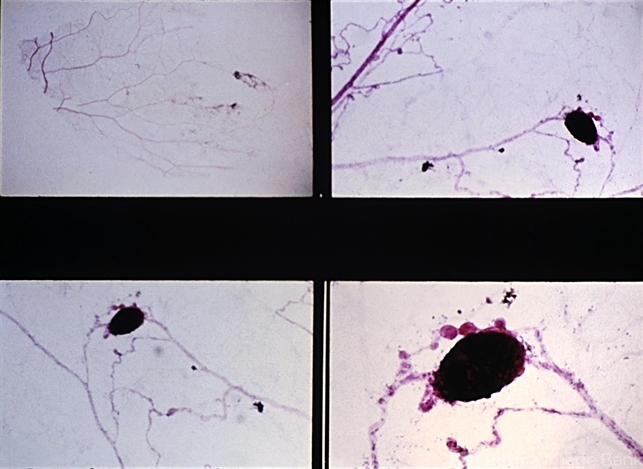

- trypsin digestion, sickle cell

- Retinal trypsin digestion preparation of sickle-cell retinopathy. There is abrupt arteriolar obstruction, and at this point arteriolar-venular looping with beading of the vessels occurs.